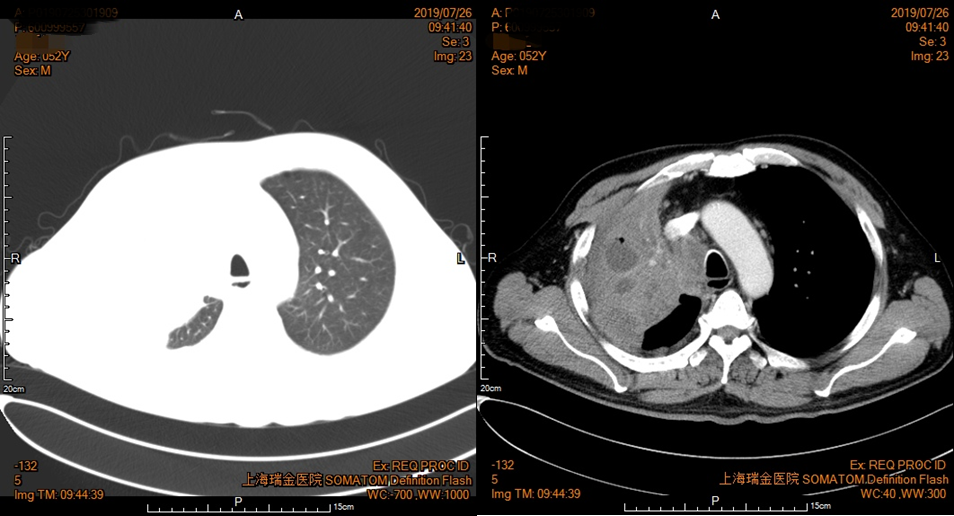

2019年7月26日胸部增强CT(图4):右肺门及上叶Ca伴右肺上叶阻塞性肺不张治疗后,较前片(5月22日)范围减小,纵隔淋巴结肿大,左肺上叶肺气肿伴肺大疱。

图4 患者胸部CT影像资料(2019年7月26日)